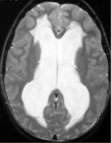

- The diagnosis of hydrocephalus is best confirmed by magnetic response imaging (MRI) of the brain. A computed tomography (CT) scan of the brain can also diagnose hydrocephalus. (But in most cases, an MRI is required afterwards.)